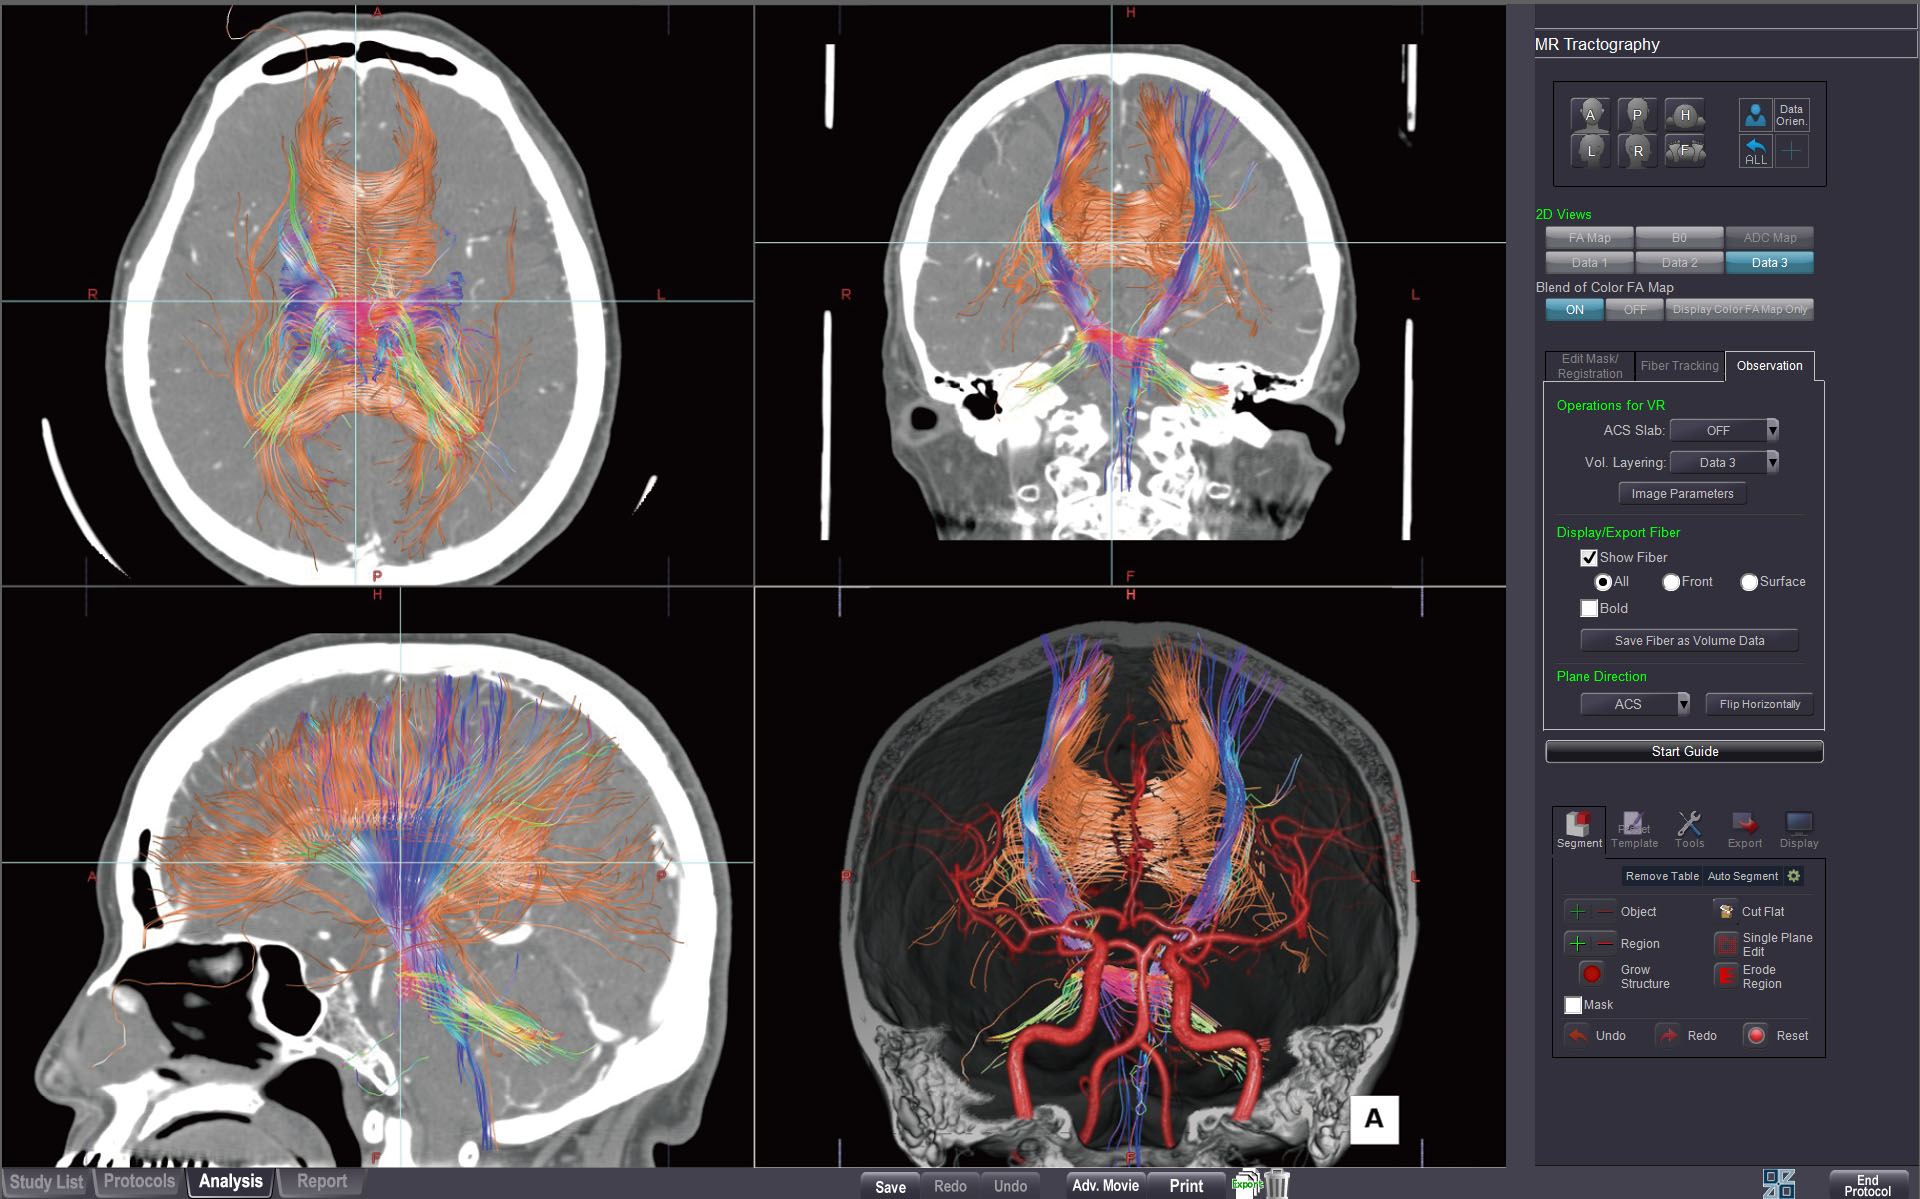

MR TRACTOGRAPHY

This protocol enables visualization of neural tracts using diffusion-weighted MR images.